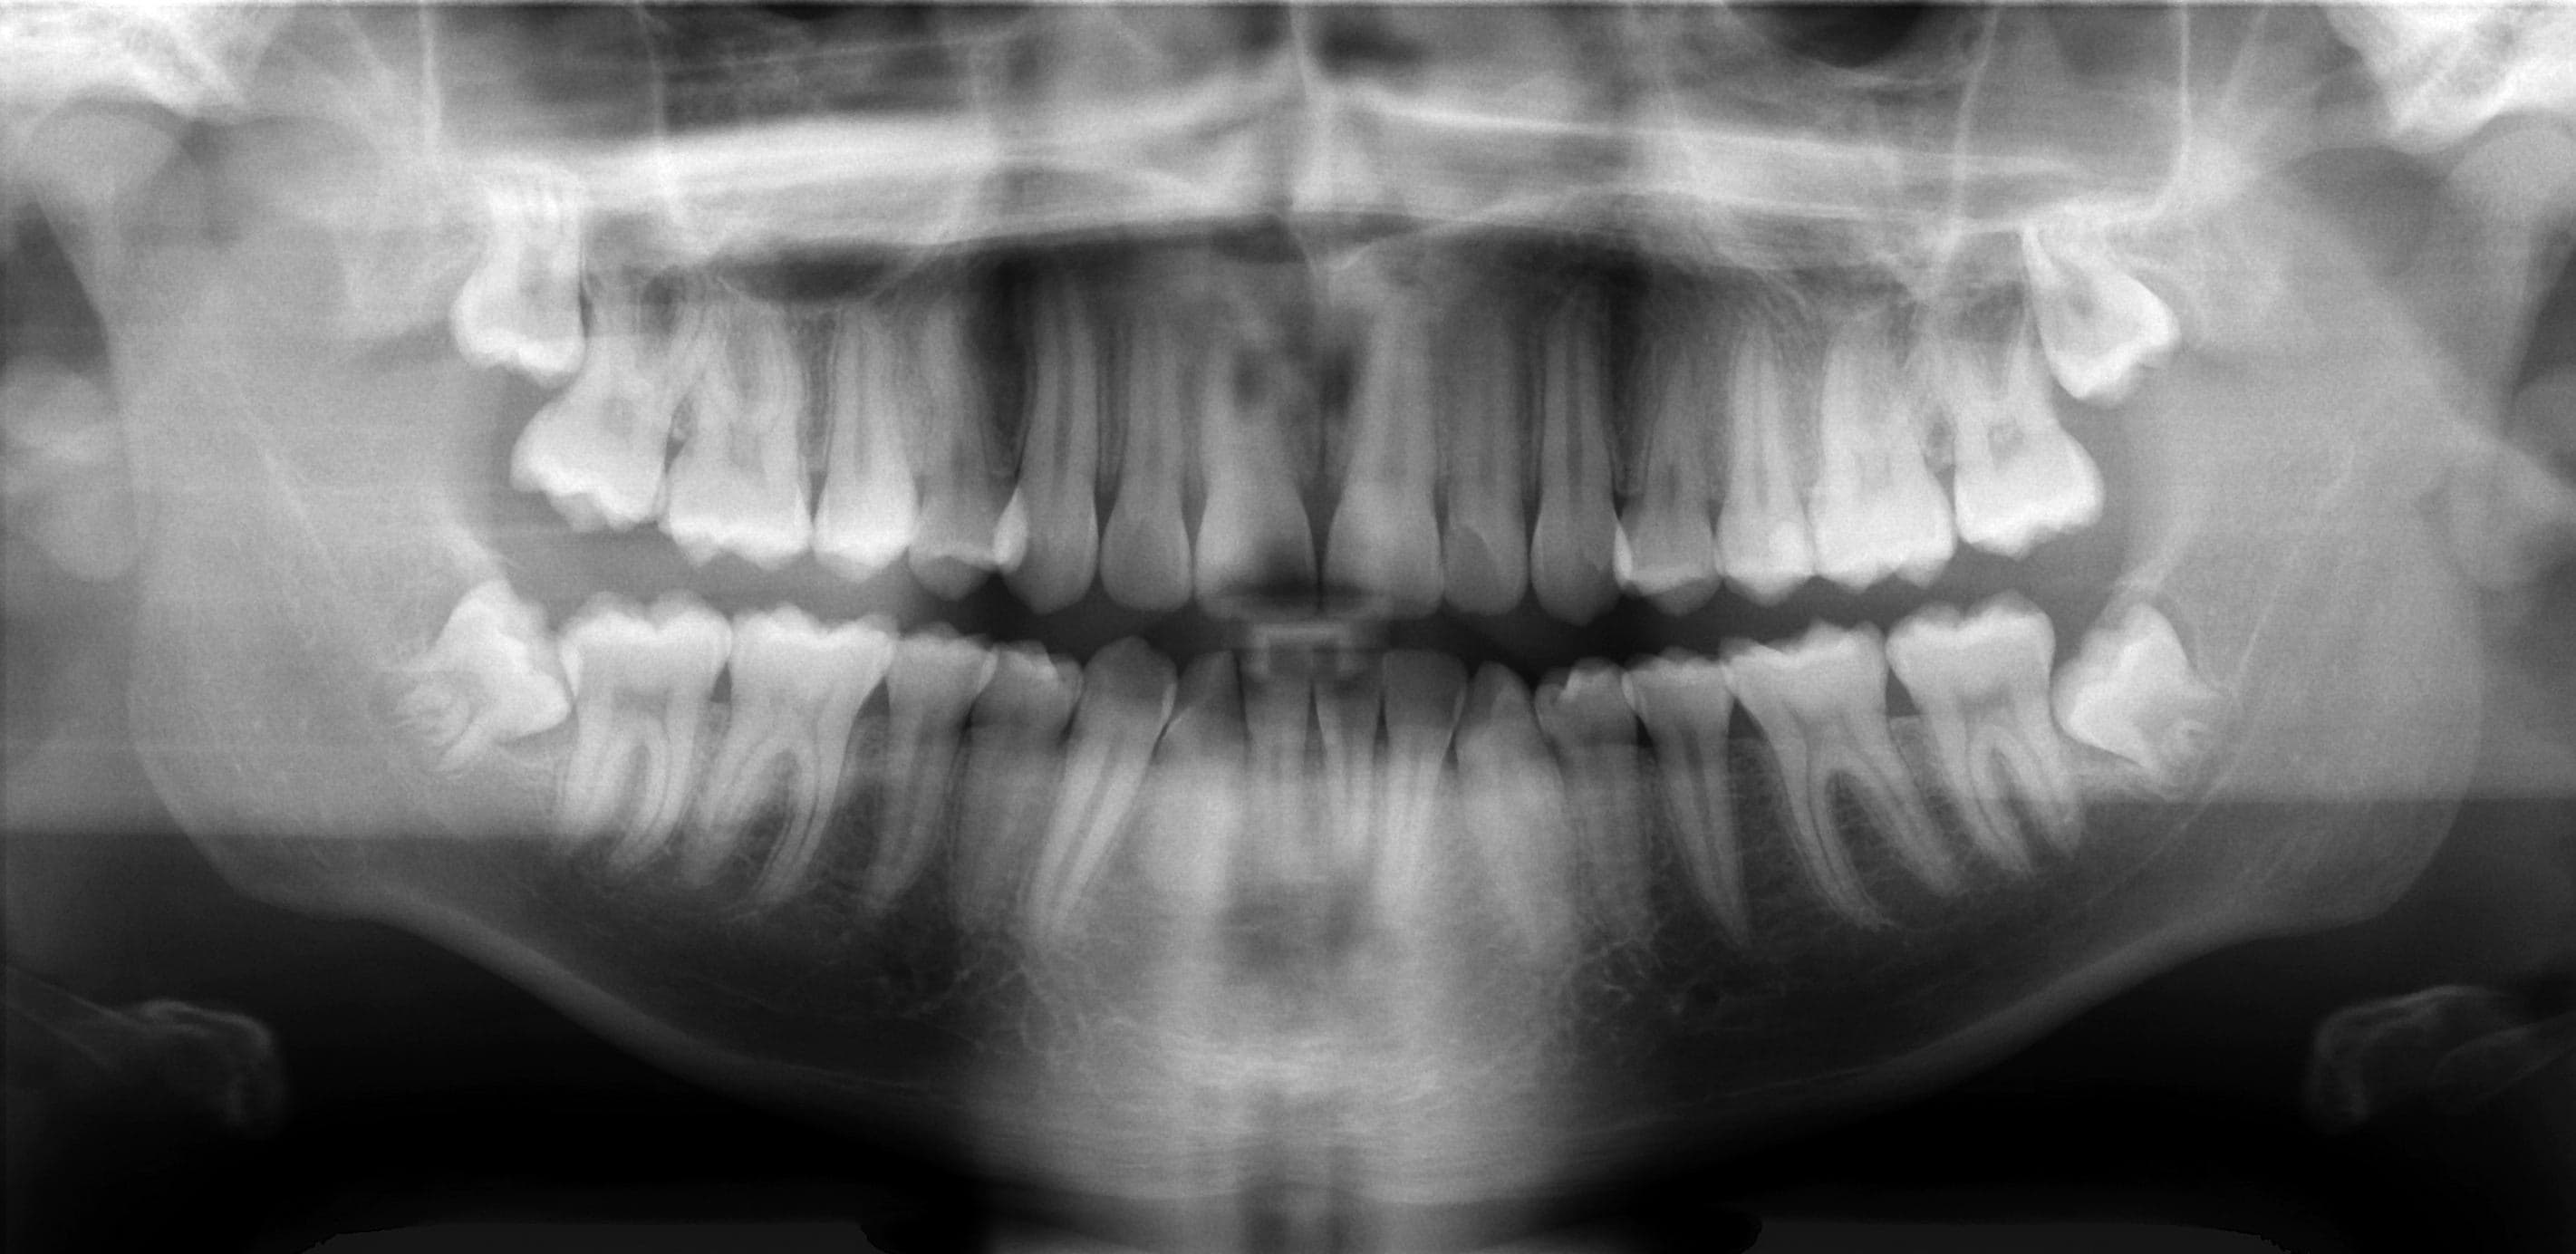

- Panoramik rontgende ilgili alt molar bolge ve yirmi yas disleriyle birlikte genel posterior tablo birlikte okundu.